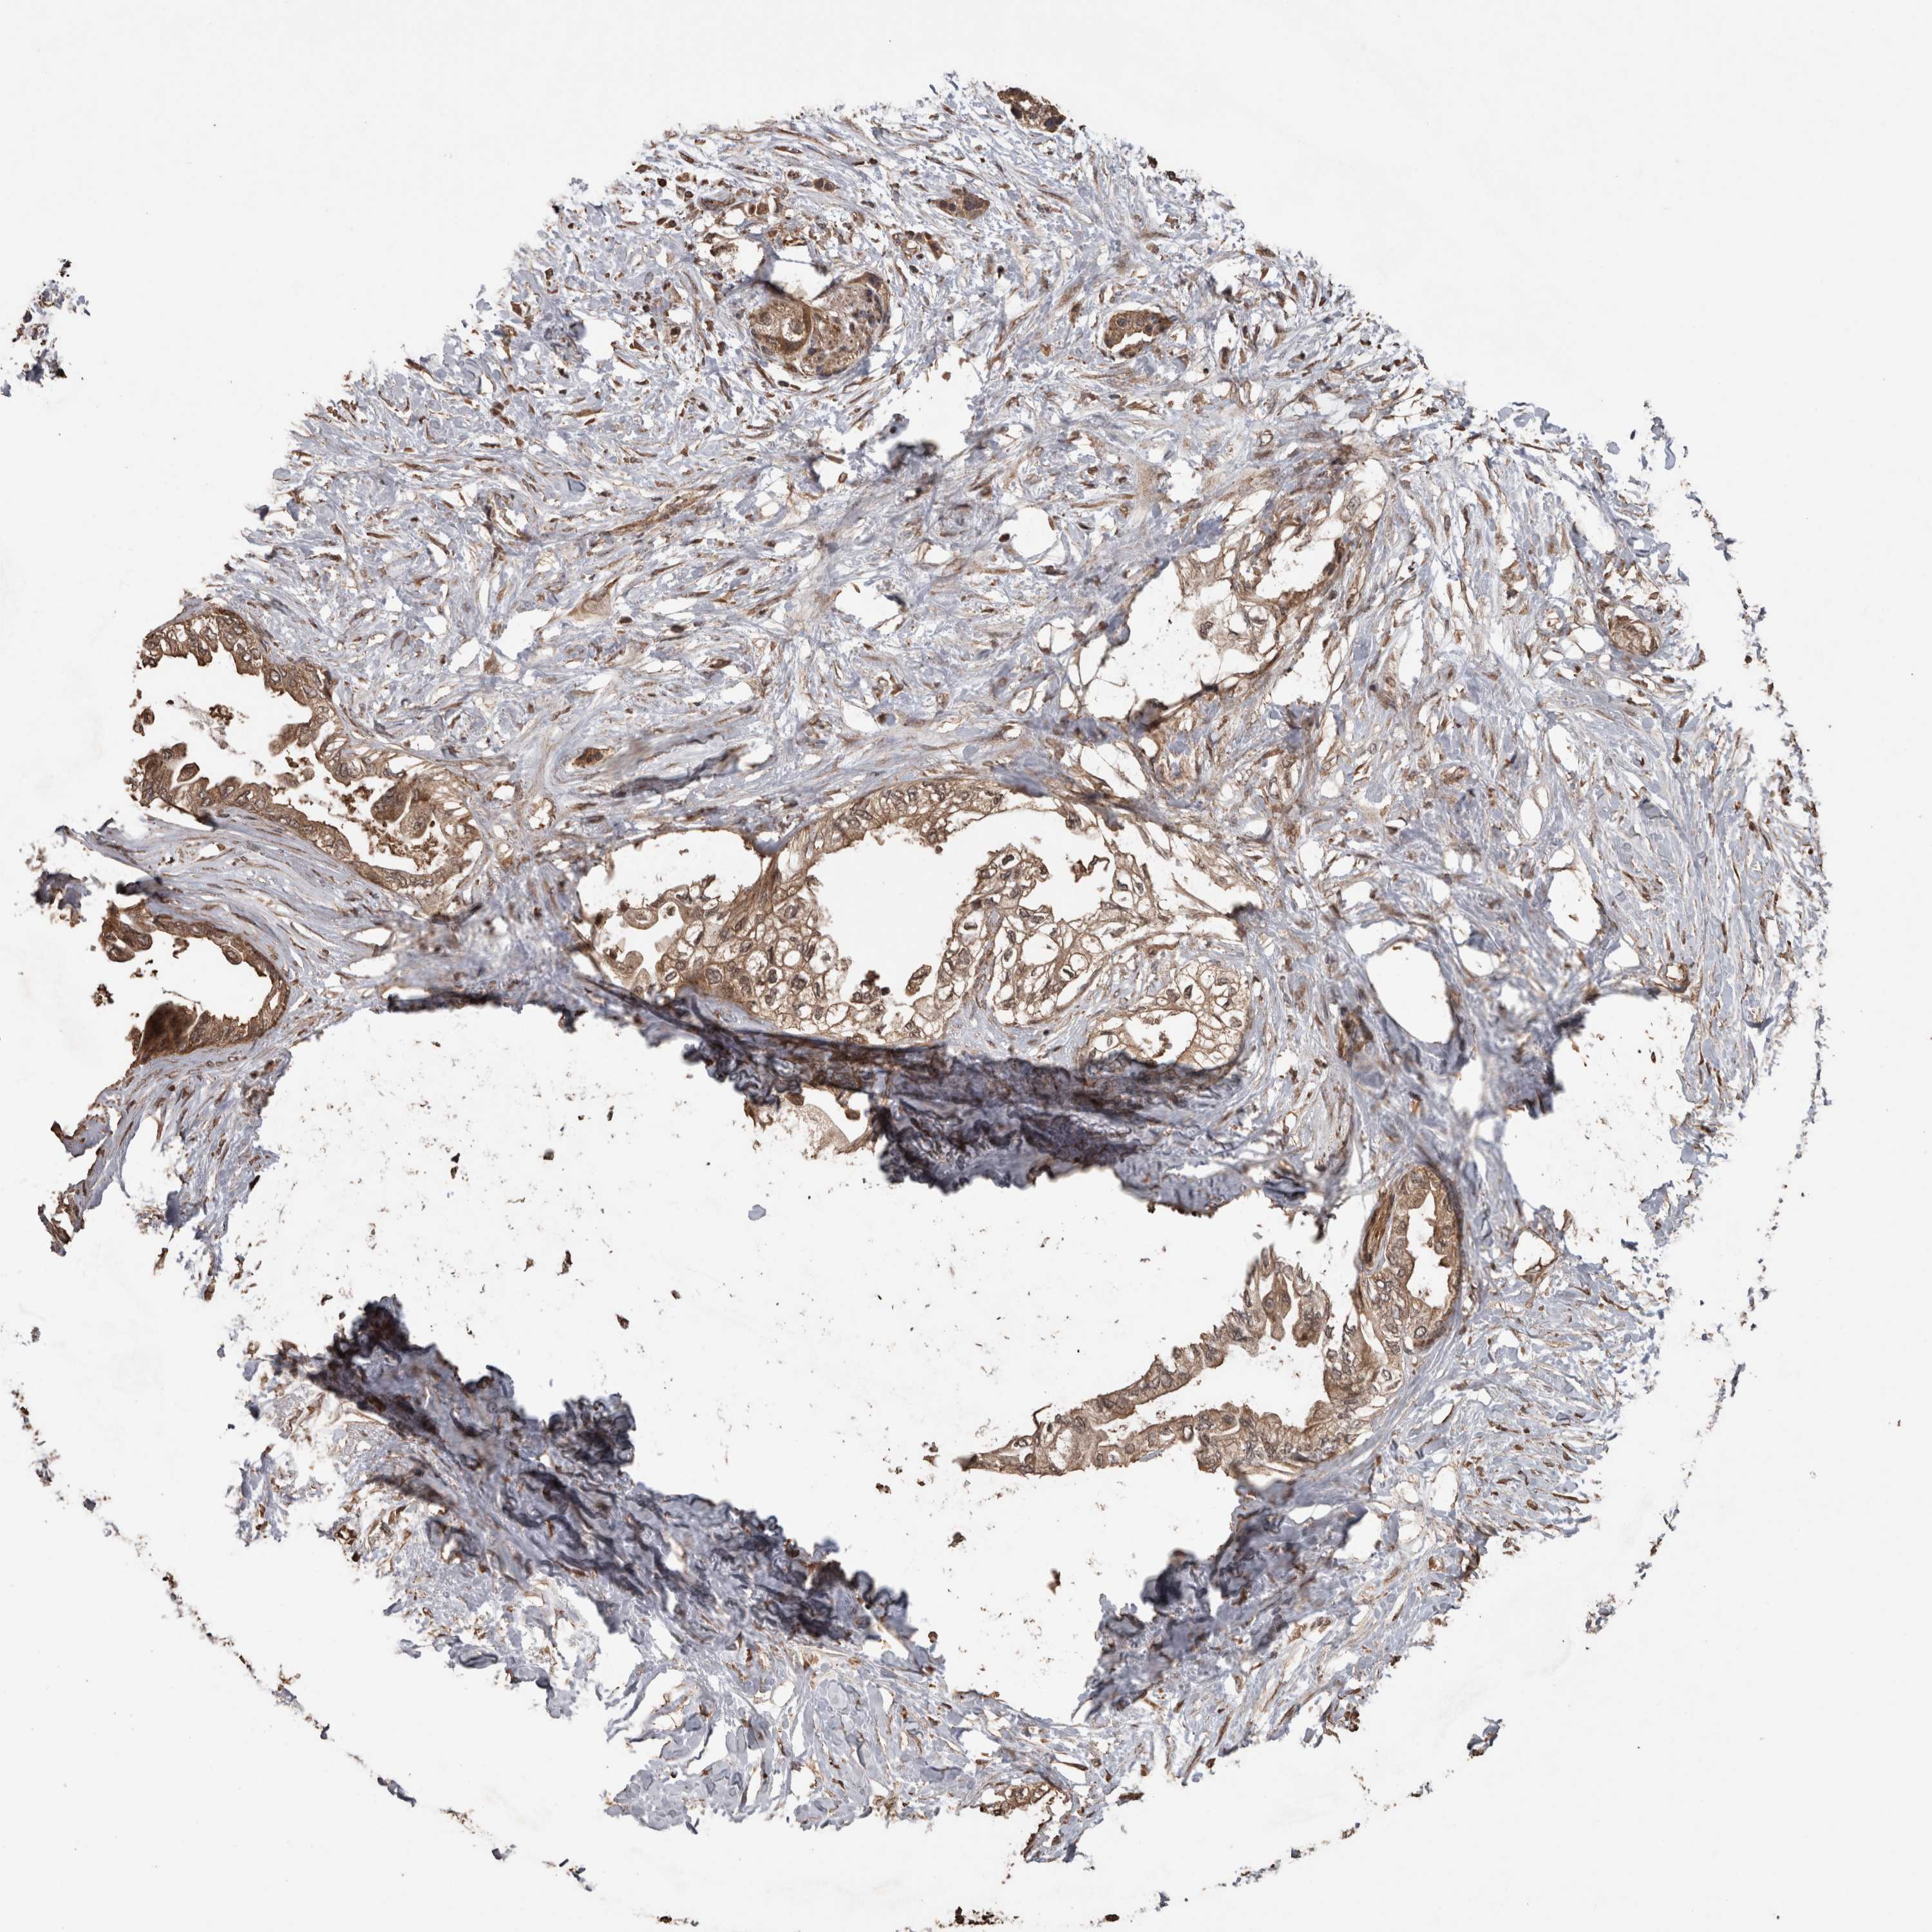

PANCREATIC CANCER - Protein expressioni

A mouse-over function shows sample information and annotation data. Click on an image to view it in a full screen mode. Samples can be filtered based on level of antibody staining by selecting one or several of the following categories: high, medium, low and not detected. The assay and annotation is described here.

Note that samples used for immunohistochemistry by the Human Protein Atlas do not correspond to samples in the TCGA dataset.

Antibody stainingi

Antibody staining in the annotated cell types in the current human tissue is reported as not detected, low, medium, or high, based on conventional immunohistochemistry profiling in selected tissues. This score is based on the combination of the staining intensity and fraction of stained cells.

Each image is clickable and will lead to virtual microscopy that enables deeper exploration of all samples and also displays staining intensity scores, fraction scores and subcellular localization as well as patient and tissue information for each sample.

Antibody HPA001931

Antibody CAB026191

Staining

High

Medium

Low

Not detected

Intensity

Strong

Moderate

Weak

Negative

Quantity

>75%

75%-25%

<25%

None

Location

Nuclear

Cytoplasmic/membranous

Cytoplasmic/membranous,nuclear

Adenocarcinoma, NOS